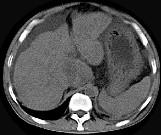

男,44岁,有乙肝病史,现腹胀,右上腹痛,消化不良,消瘦、乏力、贫血、黄疸,血清转氨酶升高,清蛋白/球蛋白比值倒置。CT、MRI检查如下图,最准确的诊断是...

问题 男,44岁,有乙肝病史,现腹胀,右上腹痛,消化不良,消瘦、乏力、贫血、黄疸,血清转氨酶升高,清蛋白/球蛋白比值倒置。CT、MRI检查如下图,最准确的诊断是 ( )

选项 A.肝硬化并腹水 B.肝硬化并腹水、再生结节 C.肝硬化腹水、肝癌 D.肝硬化并再生结节 E.肝硬化并腹水、脂肪肝

答案 B